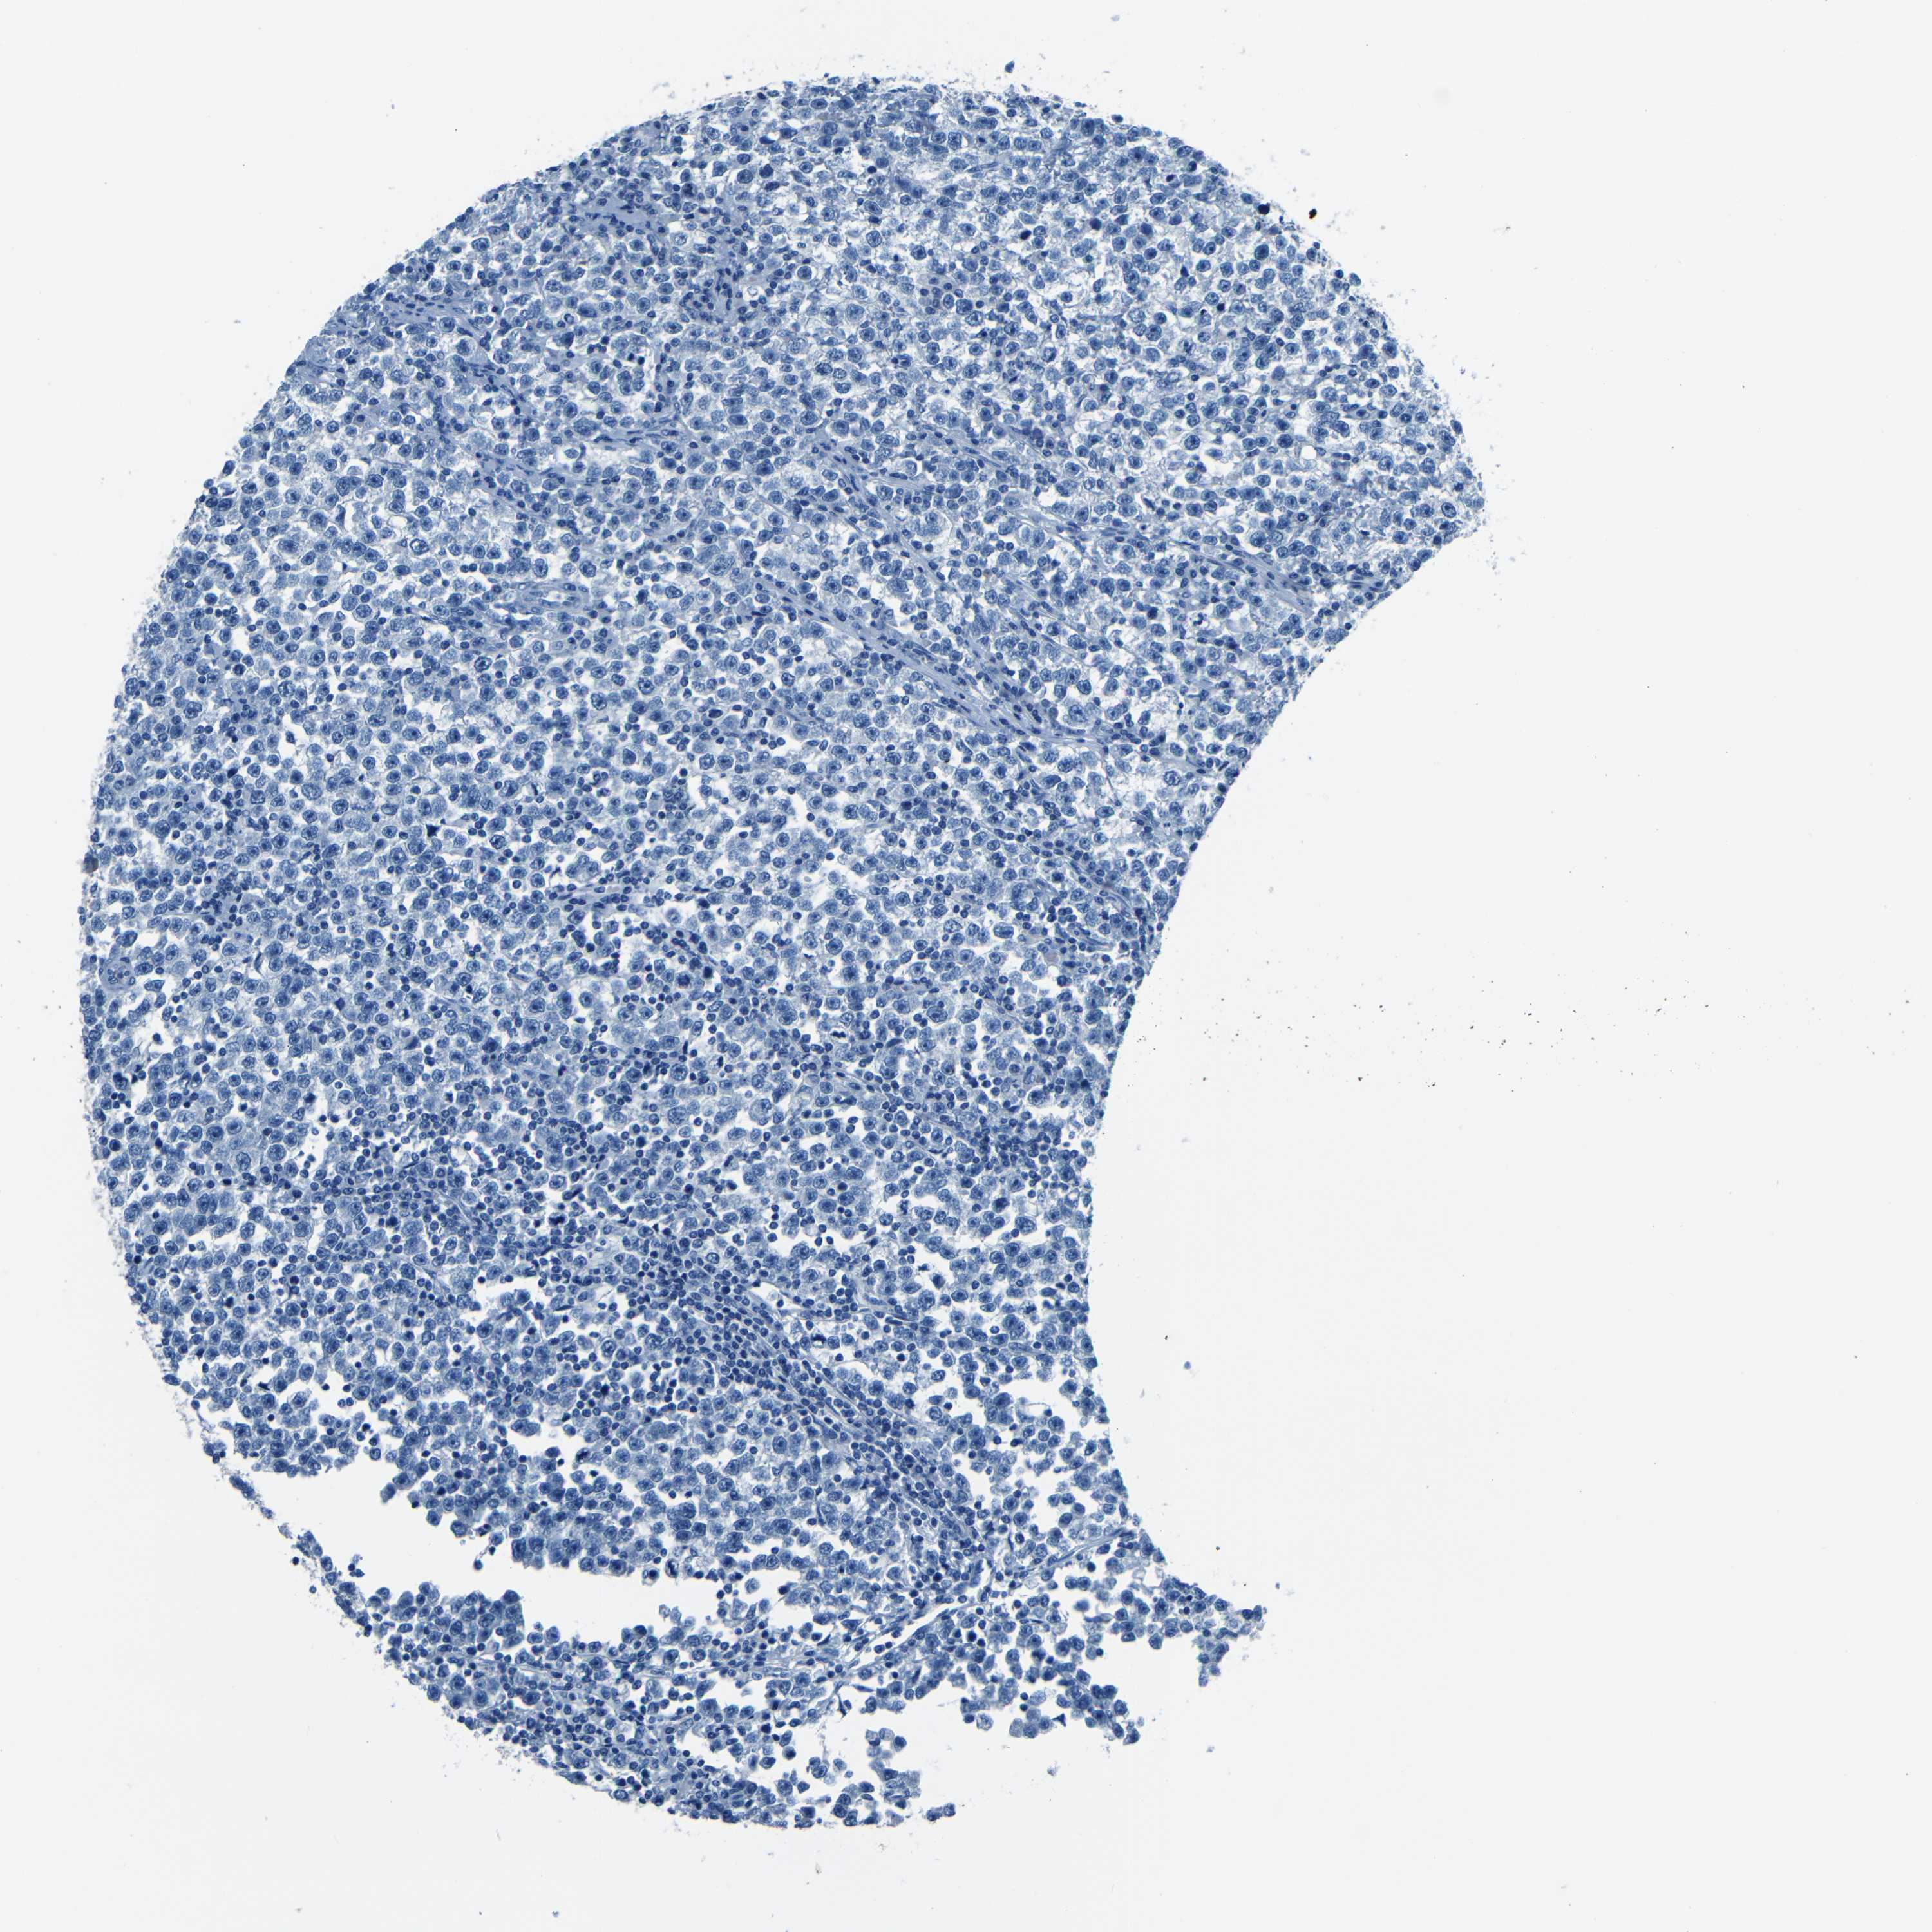

TESTIS CANCER - Protein expressioni

A mouse-over function shows sample information and annotation data. Click on an image to view it in a full screen mode. Samples can be filtered based on level of antibody staining by selecting one or several of the following categories: high, medium, low and not detected. The assay and annotation is described here.

Note that samples used for immunohistochemistry by the Human Protein Atlas do not correspond to samples in the TCGA dataset.

Antibody stainingi

Antibody staining in the annotated cell types in the current human tissue is reported as not detected, low, medium, or high, based on conventional immunohistochemistry profiling in selected tissues. This score is based on the combination of the staining intensity and fraction of stained cells.

Each image is clickable and will lead to virtual microscopy that enables deeper exploration of all samples and also displays staining intensity scores, fraction scores and subcellular localization as well as patient and tissue information for each sample.

Antibody HPA012853

Antibody CAB026401

Staining

High

Medium

Low

Not detected

Intensity

Strong

Moderate

Weak

Negative

Quantity

>75%

75%-25%

<25%

None

Location

Nuclear

Cytoplasmic/membranous

Cytoplasmic/membranous,nuclear

Carcinoma, Embryonal, NOS

Seminoma, NOS